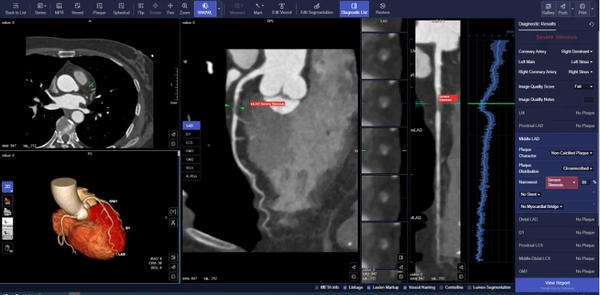

クレアボが提供する「CoronaryDoc」では,CT装置の撮像データを,人手を介さずに画像解析が可能となり,約3分以内で心臓CTの画像処理をシステム側で実施し,診断に必要な画像や構造化レポートを保存することができる[7]。また,AIアルゴリズムは冠動脈領域の描出から,狭窄が疑われる部位やプラークの識別を行い,それらの情報を構造化レポートとして作成する。

▼ 解析例

※ 実際の製品の表示とは異なる場合がある。